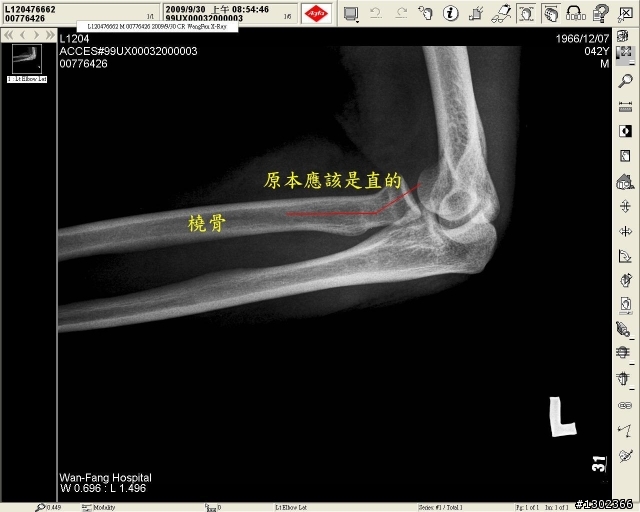

基本消費~~兩根骨頭買單(右手橈骨+右肩鎖骨)~~

我就現PO兩張聞香一下嚕

M01傳統~~有圖有真相